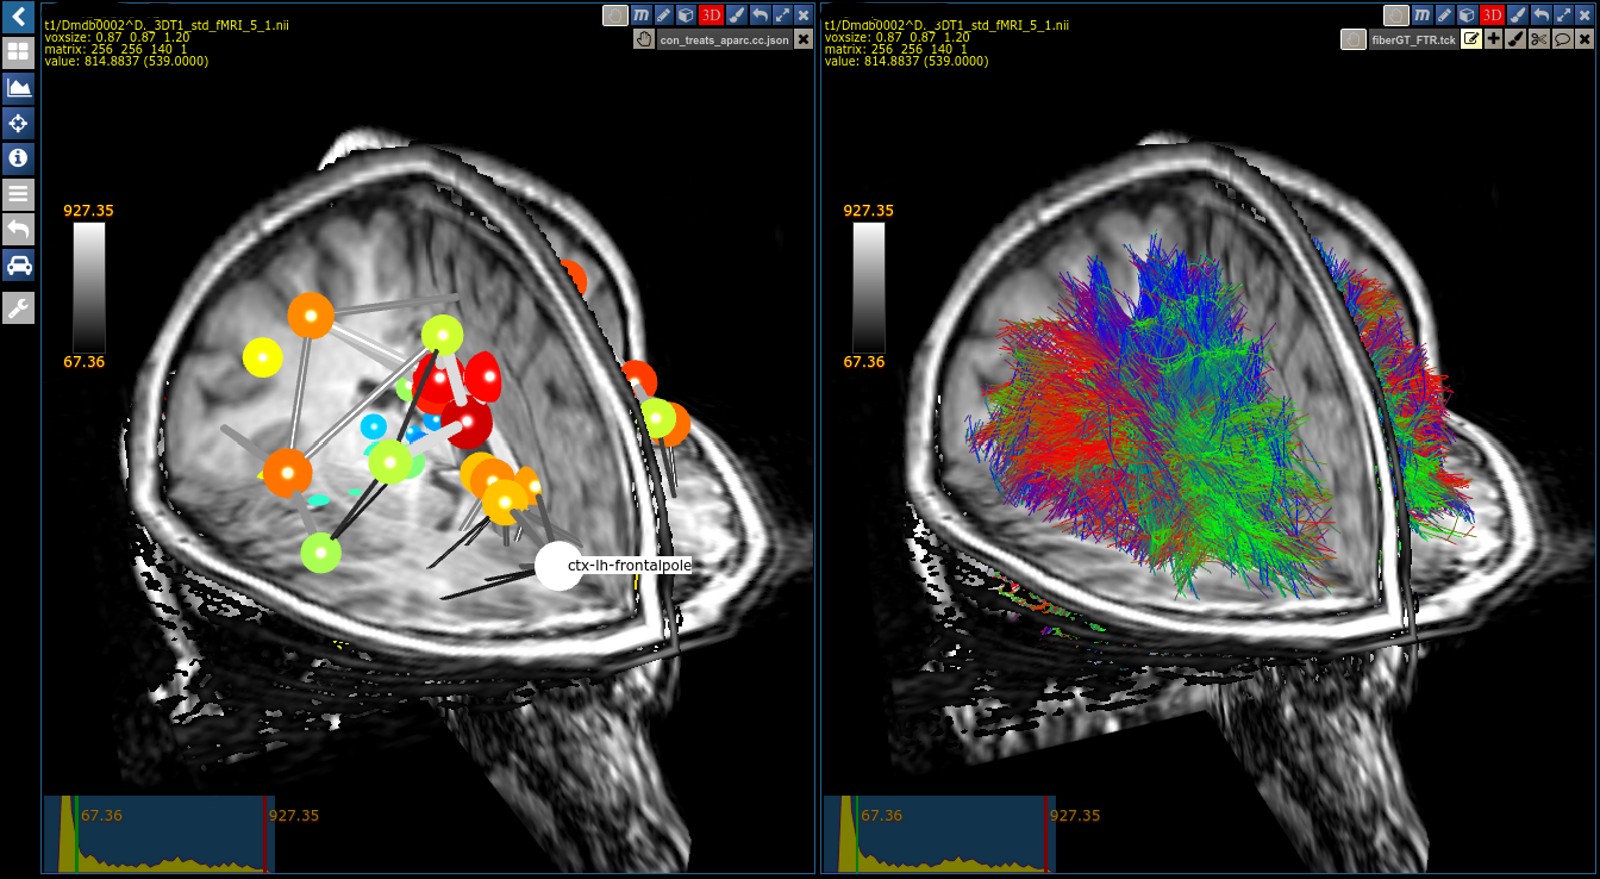

MRI Tractogram Fibers: The fiber viewer provides features beyond the standard: Navigate in 3D and follow tracts interactivley and in real time using the optimized octtree functionality.

MRI Tractogram Connectivities: Navigate through the brain and explore the connectivites.

MRI Tractogram Segmentations: Interactivley segment tracts in real time based on a machine learning algorithm.